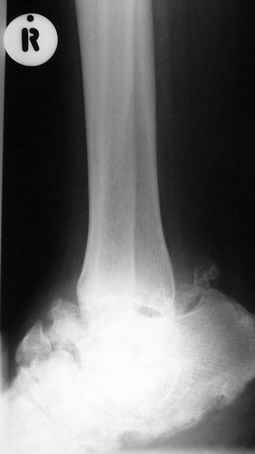

Уажаемые коллеги,представленные рентгенограмммы я показывал на нашем х-рей митинге - они были встречены с большим интересом.. Ну, ещё бы - я сам эту патологии встречал раза три за всю свою долгую жизнь:

Кто шустрый - при какой патологии встречается так называемые "суставы Шарко"?Второе приобретение доктора Эмануэла мне понравилось своим романтическим названием: Candle bone - <кость-в-виде-оплывающей-свечи> : Просто редкая патология: